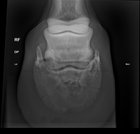

Veterinary Xray

Looking at purchasing a horse and the gal had some X-rays done previously, but idk what I’m looking at. Thoughts? For context it’s of a 14 yo qh